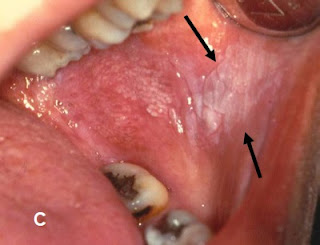

බුලත්විට කෑම සහ මුඛ පිලිකා / Betel Nut Chewing and Oral Cancer